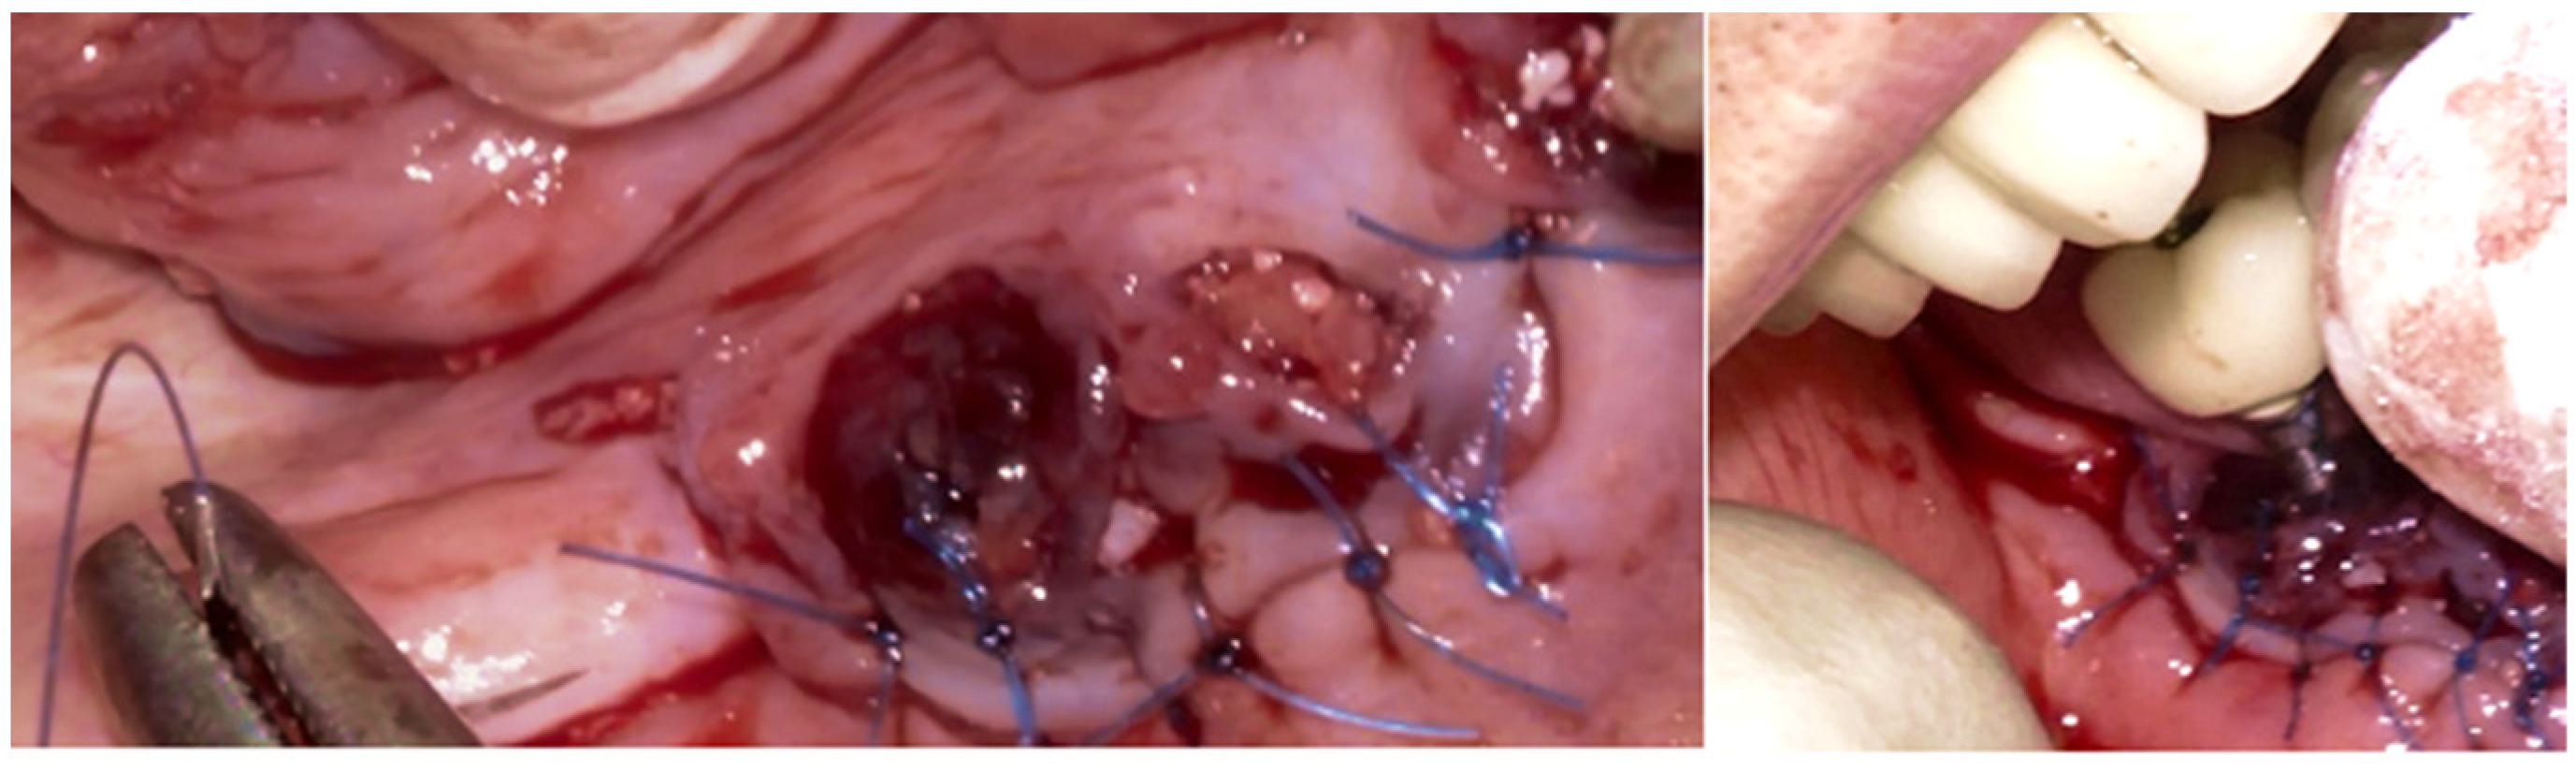

The Quadrant protocol for peri-implantitis treatment was applied, as previously described. The dental implants #42–#47 received the insertion of the iMPACT to remove residual biofilm and contaminants directly from the implant surface, effectively renewing them without the need for implant retrieval. This step revitalized the implant surface, eliminating factors that contribute to peri-implantitis and establishing a stable foundation for healing (Figure 22a–c). The iMPACT’s cutting blades cut the implant surface and a portion of the bone (a controlled procedure). The granulation tissue, residual biofilm, and contaminants were meticulously removed with the tool, facilitating the restoration of implant surface integrity.

Figure 22. (a) iMPACT tool was placed for implantoplasty; (b) iMPACT spinning to remove the contaminated threads, machining the implant surface; (c) Result obtained after treatment.